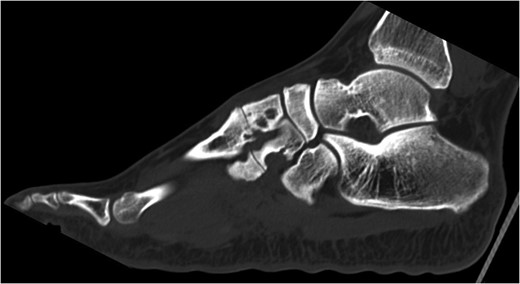

The patient had CT scans conducted that showed erosive processes around the intermediate and lateral cuneiforms extending into the plantar aspect (Fig. 2). These appearances were similar to the previous MRI taken 8 months ago. It was felt this could be due to joint-based erosive chronic inflammation and atypical infection such as TB. However, the patient had no TB symptoms and a recent negative Heaf test.

CT scan of left foot. Erosive bony changes are visible of the intermediate and lateral cuneiforms and the corresponding metacarpal bases. These erosions vary in size from 5 to 7 mm.